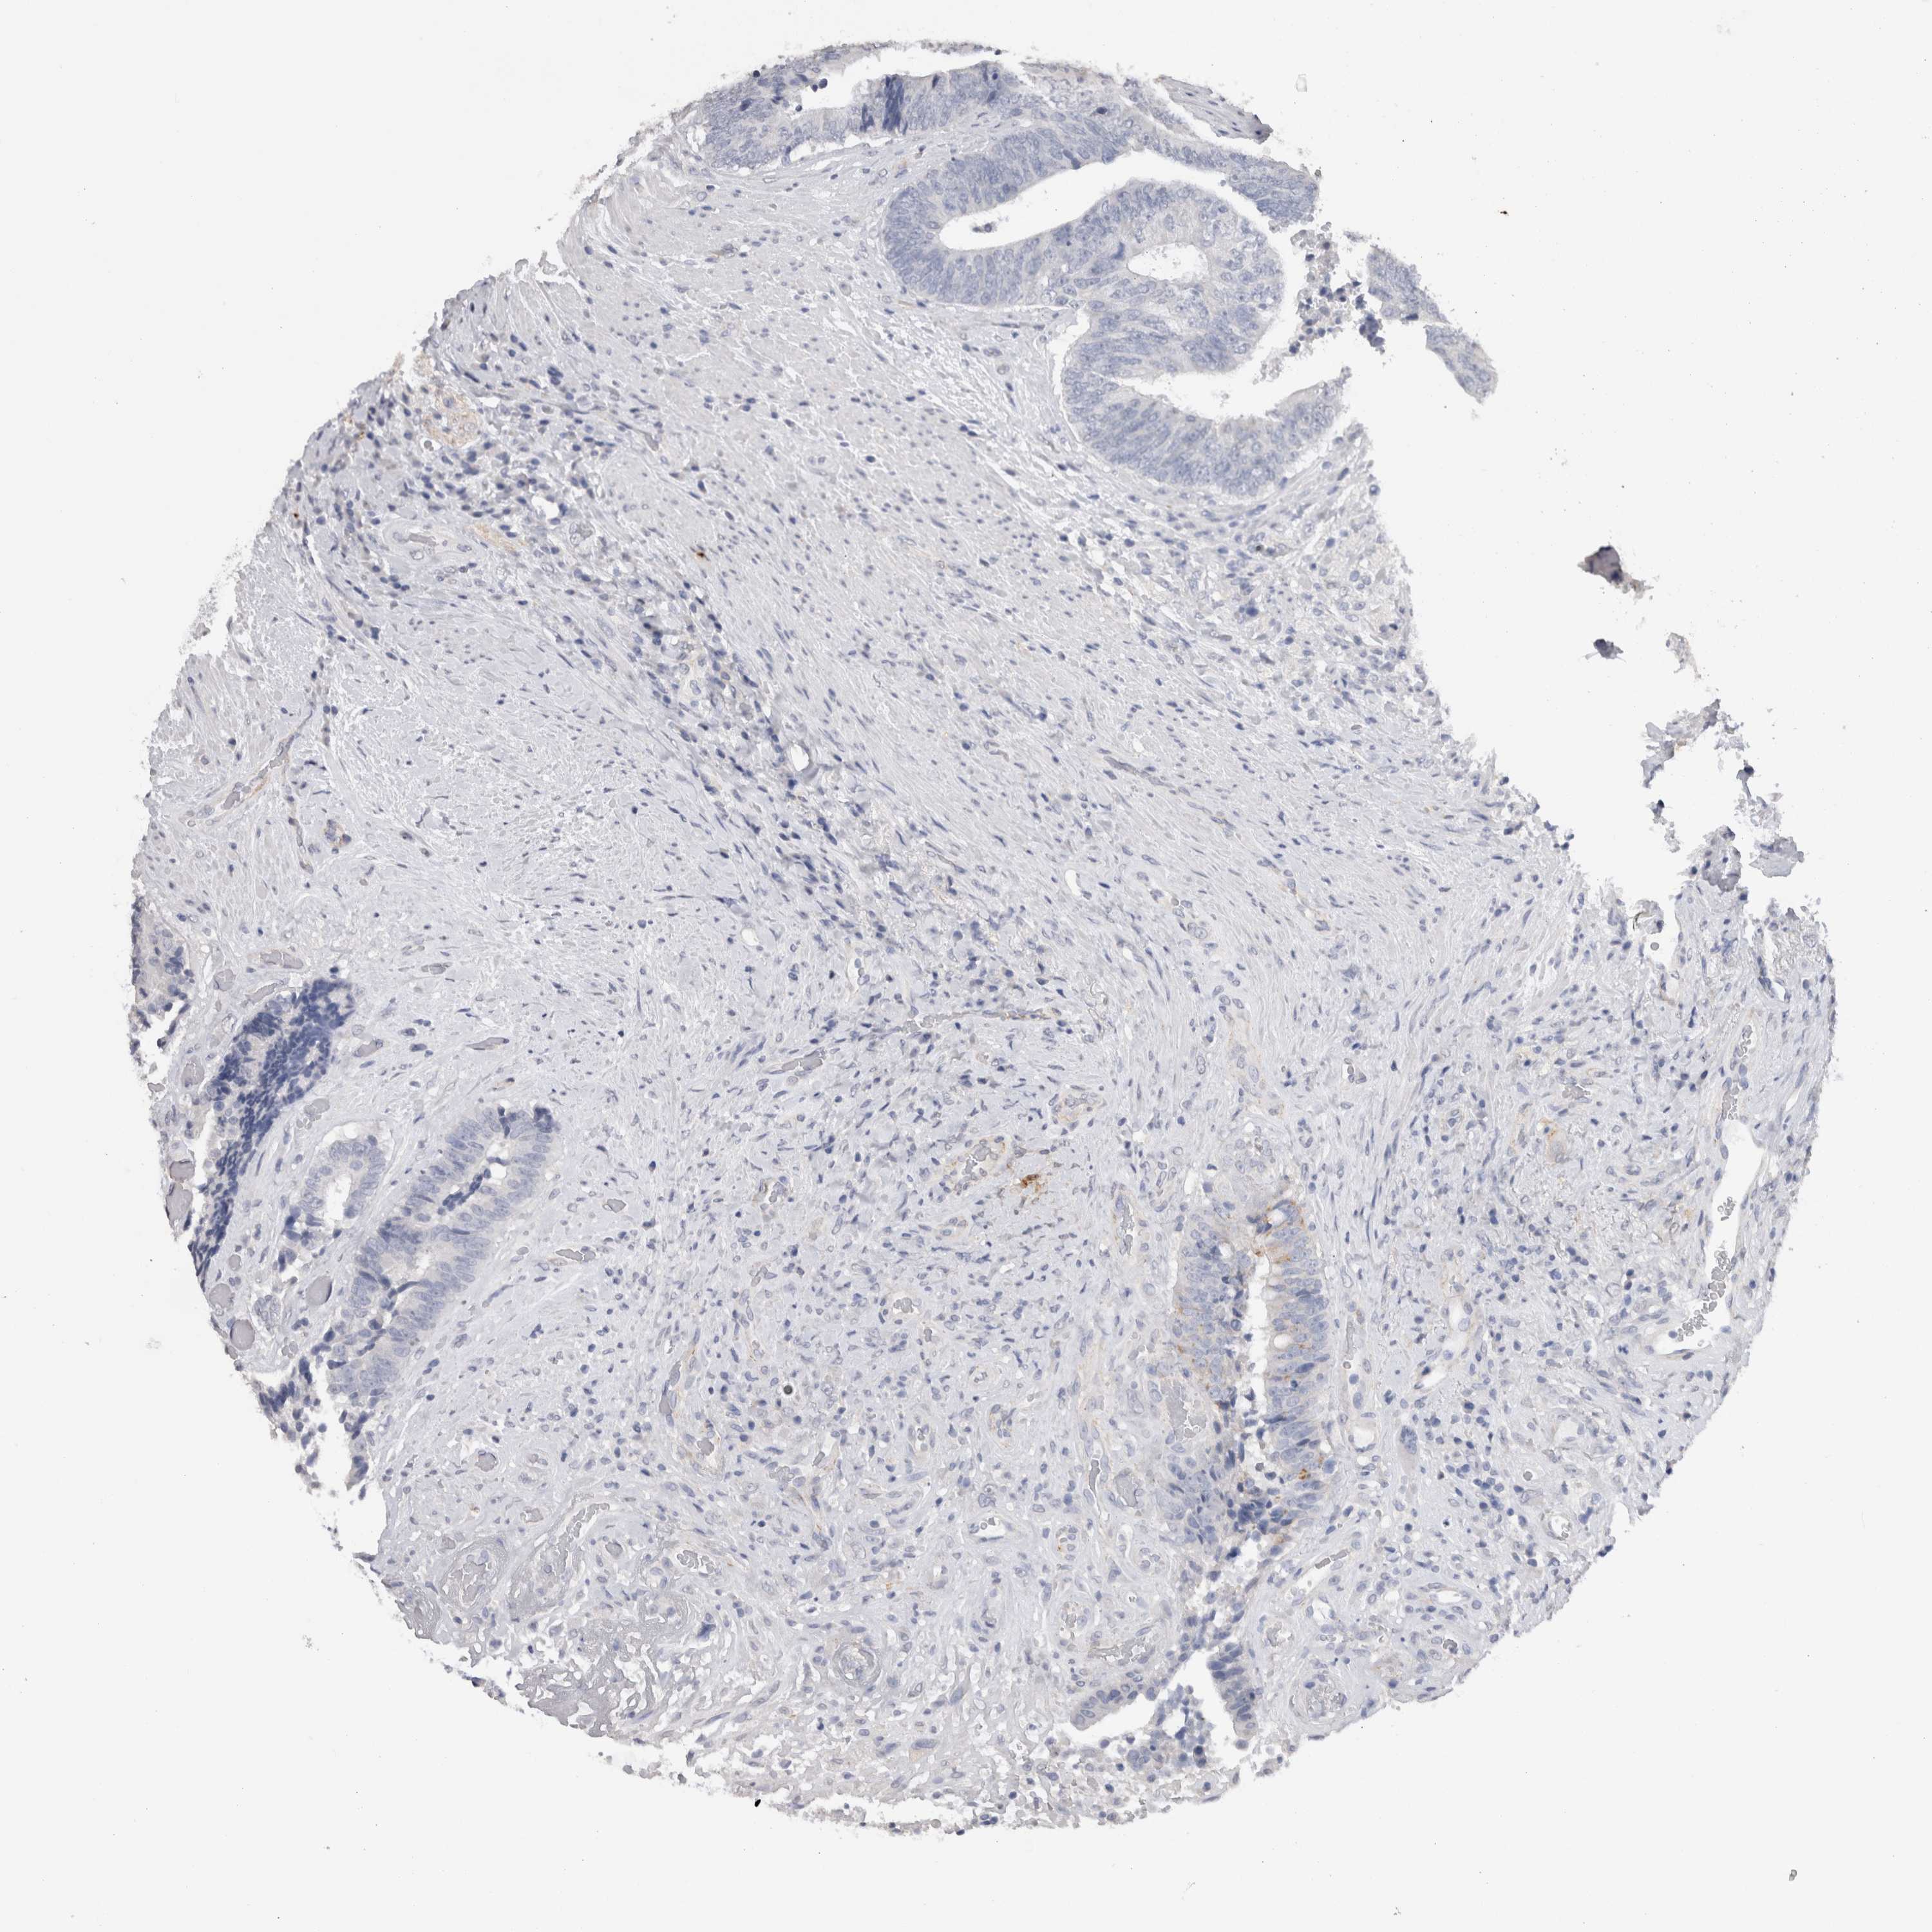

CANCER COLORECTAL CANCER Show tissue menu

Colorectal cancer

Human cancer

Colon adenocarcinoma